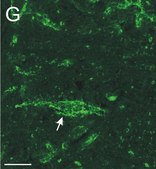

Anti-Chondroitin Sulfate Proteoglycan Antibody, Brain (core protein), clone Cat-301 detects level of Chondroitin Sulfate Proteoglycan & has been published & validated for use in IP, WB, IC, IH.

Immunohistochemistry: 1:500-1:2,000 on 4% paraformaldehyde fixed frozen tissue.

The antigen recognized by this clone, CAT-301 is a proteoglycan that is developmentaly regulated, high molecular chondroitin sulphate proteoglycan found on the extracellular surface of mammalian neurons. It is expressed late in development and although no definitive role has been identified for CAT-301, it is believed to have a role in the stabilisation of synaptic structure.